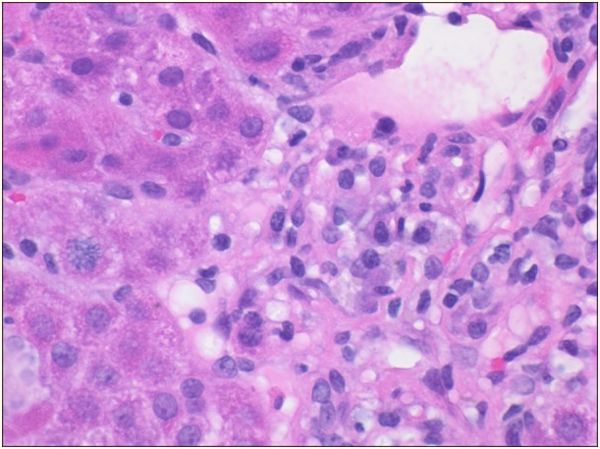

腹部超声多普勒超声检查:没有发现肝脏或胆道异常,但有轻微的脾肿大。肝脏活组织显示明显的玫瑰花结,浆细胞增多,窦状隙成熟淋巴细胞轻微增加,2期门静脉周围纤维化,无桥接或肝硬化结节,无嗜酸性粒细胞存在,无可染色铁、铜或A1AT小球。这些组织学发现与中度至重度急性慢性肝炎(总体3至4级)一致,提示自身免疫性肝炎。根据这些发现和整体临床表现,患者被诊断为继发于米诺环素的药物诱导的自身免疫性肝炎。

图2 血浆细胞增多